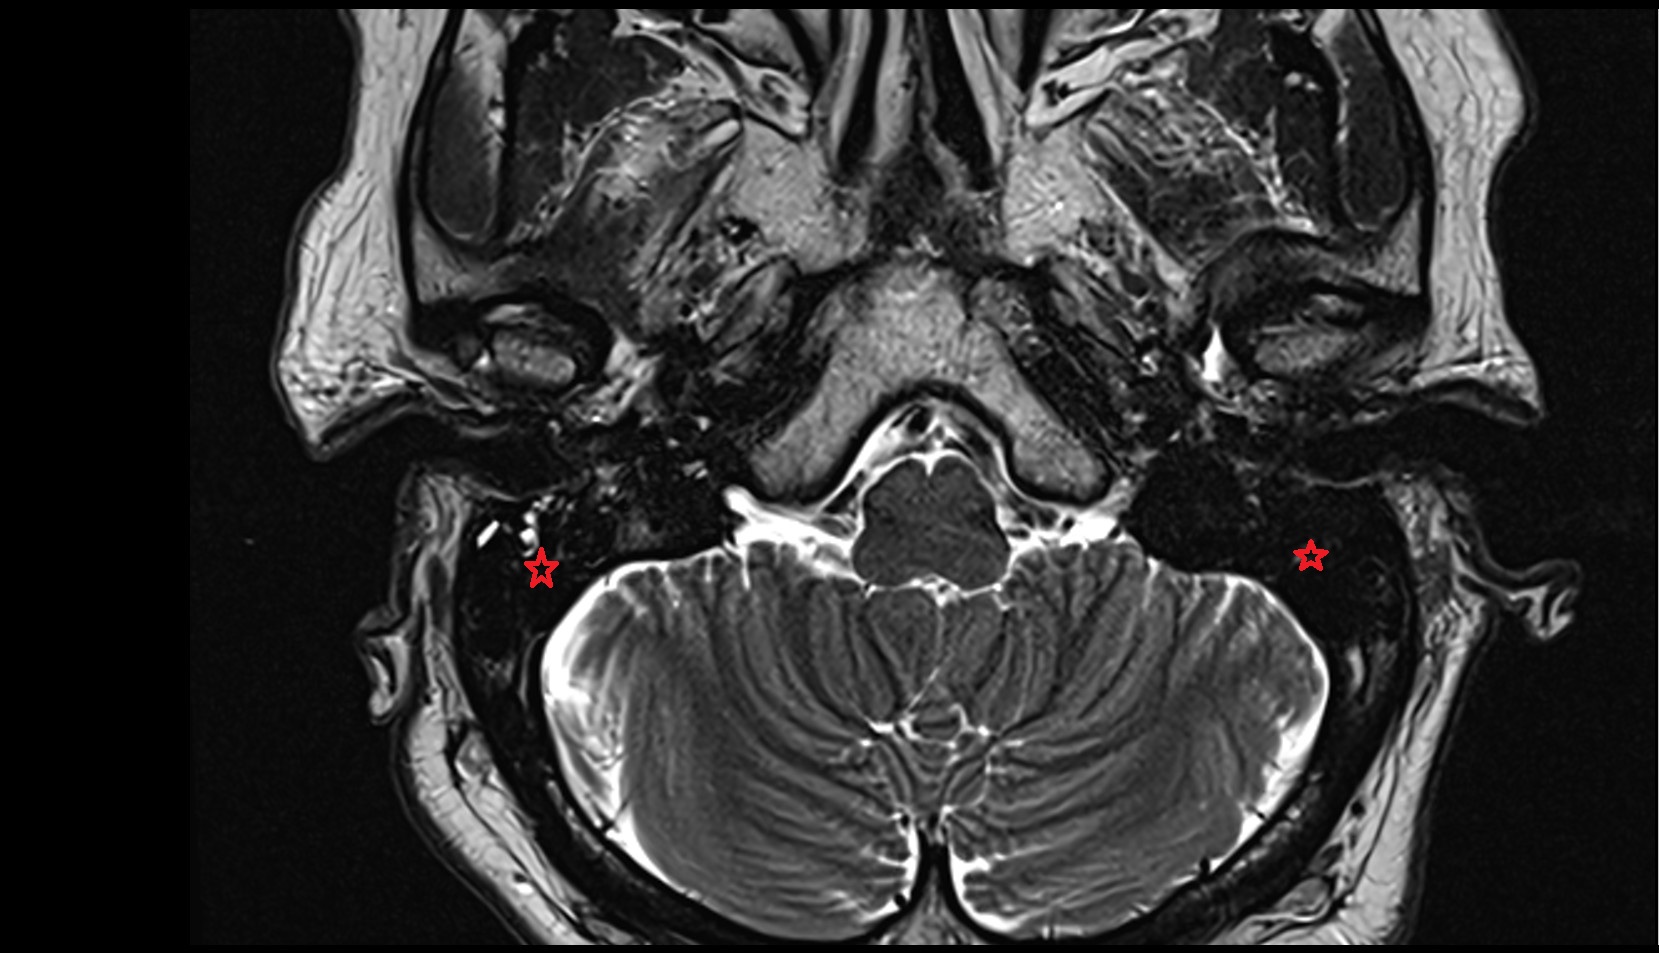

- Cerebellopontine angle

- Lateral cerebellomedullary cistern

- Cerebellopontine cistern

- Lateral aperture of fourth ventricle (foramen of Luschka)